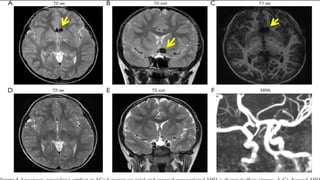

INVESTIGATIONS

• CT scan

• CT angiogram

• MRI and MRA

• DSA